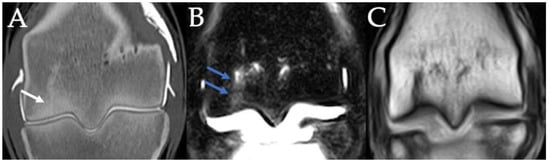

3.4. PSG Subchondral Bone Defects

3.5. PSG Cartilage Defects

3.8. Fetlocks with Possible Fracture Pathology